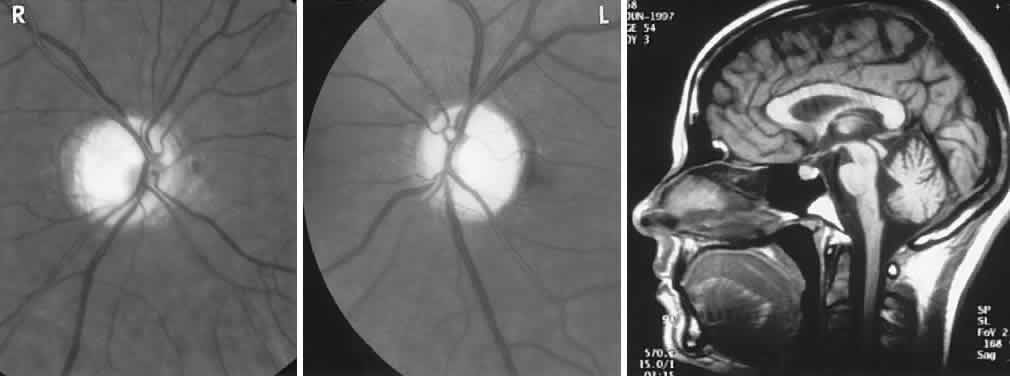

Optic nerve involvement may occur in the mucopolysaccharidoses (MPS), taking the form of optic atrophy or papilledema. Although true papilledema doubtlessly occurs in association with hydrocephalus seen in these disorders, there are other instances of “papilledema” in which fundus descriptions or photographs are not convincing. Goldberg and Duke35 reported the ocular histopathologic findings in a patient with Hunter's syndrome (MPS II), in which premortem examination included the observation of “bilateral chronic papilledema.” On microscopic examination, the optic nerve was normal, despite marked retinal pigmentary degeneration, showing neither consecutive atrophy nor changes compatible with chronic papilledema. Similarly, Kenyon and colleagues36 reviewed the systemic mucopolysaccharidoses and included an instance of a 26-year-old man with Hunter's syndrome (MPS II), whose ophthalmoscopic examination revealed “blurred disc margins in both fundi (without venous congestion, hemorrhages or exudates) compatible with mild chronic papilledema,” but no further comment was made in elucidation of this finding. Hunter's syndrome is an X-linked recessive disorder characterized by facial and skeletal dysmorphism, stiff joints, and mental slowing. Deafness and chronic disc edema occur, without raised intracranial pressure, and mucopolysaccharide deposition in the sclera and optic nerve septa, especially at the lamina cribrosa, is described.37 MRI may disclose large multifocal cystic areas of hypointense or hyperintense signals in white matter, including the corpus callosum, likely reflecting deposition of mucopolysaccharide and increased fluid content.38

Mailer39 reviewed 16 patients with optic atrophy in gargoylism and concluded that communicating hydrocephalus was the most frequent cause. Although hydrocephalus has long been recognized to occur in mucopolysaccharidosis, it is uncovered more frequently at autopsy than clinically. Goldberg and associates40 reported a case of Maroteaux-Lamy syndrome (MPS VI) with hydrocephalus and papilledema, treated with a ventriculojugular shunt. Those authors discussed the following possible pathogenetic mechanisms of visual dysfunction due to optic nerve involvement in mucopolysaccharidosis: optic atrophy secondary to glaucoma, retinal pigmentary degeneration, or mucopolysaccharide deposition in the retinal elements; infiltration of the nerve substance or meninges; narrowing of the optic canals; and hydrocephalus, with or without papilledema. Retinal pigmentary dystrophy occurs in MPS I-H (Hurler), MPS III (Sanfilippo), and MPS I-S (Scheie), all resulting from storage of heparan sulfate.